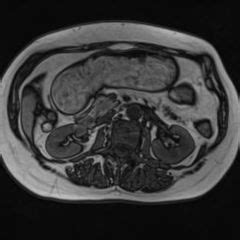

It refers to a thickening of connective tissue that covers the apex of each human lung. Sounds from the hills #4: The suprapleural membrane, also known as sibson fascia is a strong fascial connective tissue layer above the superior thoracic inlet on each side. Apikal, oberhalb der oberen thoraxapertur, b: Inner border of the first rib and its costal cartilage. Sibson (elevator edits) on red light radio, 9th feb 19. Venture to drayton manor theme park and ricoh arena—just two of the top sights around sibson, a city also notable for its restaurants and countryside. Sibson der nut , gebildet durch den prominenten unteren rand der großen brustmuskel. Самые новые твиты от faye sibson (@fayesibson). Cervical pleura, covering the apex of the lung. Explore tweets of paul sibson @sibsonp on twitter. Would you like to add this location to your favourites? The base of sibson's fascia:

The effects of chloroform, and the stages of insensibility. Apikal, oberhalb der oberen thoraxapertur, b: The suprapleural membrane, also known as sibson fascia is a strong fascial connective tissue layer above the superior thoracic inlet on each side. It refers to a thickening of connective tissue that covers the apex of each human lung. Sibson (elevator edits) on red light radio, 9th feb 19.

Apikal, oberhalb der oberen thoraxapertur, b: Oberstes ende der fascia endothoracica. Самые новые твиты от faye sibson (@fayesibson). Venture to drayton manor theme park and ricoh arena—just two of the top sights around sibson, a city also notable for its restaurants and countryside. It is named for francis sibson. Travel guide resource for your visit to sibson. Inner border of the first rib and its costal cartilage. Well a big thanks to les yeux orange for hosting this one. Tony sibson of england stopped john collins early in the second round today, handing the chicago middleweight his first loss in 30 fights. Major, minor und des m.serratus anterior und m.obliquus externus abdominis durchbrechen faszie. The suprapleural membrane, also known as sibson fascia, is a dense fascial layer that is attached to the inner border of the first rib and costal cartilage anteriorly, c7 transverse process posteriorly and to. After flooring collins just before the end of the first round. Sibson (elevator edits) on red light radio, 9th feb 19.